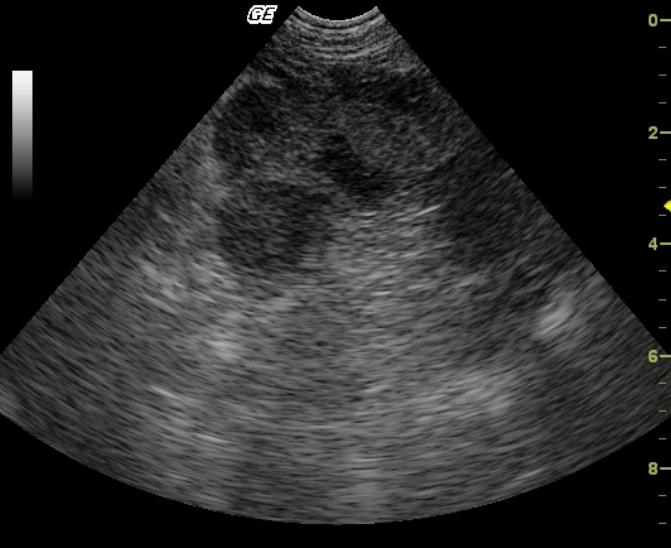

A 10 year old MN Pug was presented for the evaluation of anorexia, vomiting, diarrhea, and pollakuria. No abnormalities were noted on the physical exam. The CBC showed a neutrophilia, monocytosis, and thrombocytopenia. A serum biochemical profile revealed elevated serum alkaline phosphatase, elevated ALT, elevated AST, elevated GGT enzyme activities as well as hypercholesterolemia.